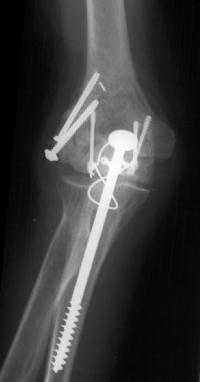

She began immediate protected motion and discontinued splint use at two weeks, despite recommendations to the contrary. These films are two months postop:

Lateral column not yet fully consolidated on Xray, but clinically healed.